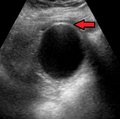

Acute cholecystitis with gallbladder wall thickening, a large gallstone, and a large gallbladder

Right upper quadrant abdominal ultrasound is most commonly used to diagnose cholecystitis.[1][22][23] Ultrasound findings suggestive of acute cholecystitis include gallstones, fluid surrounding the gallbladder, gallbladder wall thickening, dilation of the bile duct, and sonographic Murphy's sign.[2] Given its higher sensitivity, hepatic iminodiacetic acid (HIDA) scan can be used if ultrasound is not diagnostic.[2][13] CT scan may also be used if complications such as perforation or gangrene are suspected.[13]